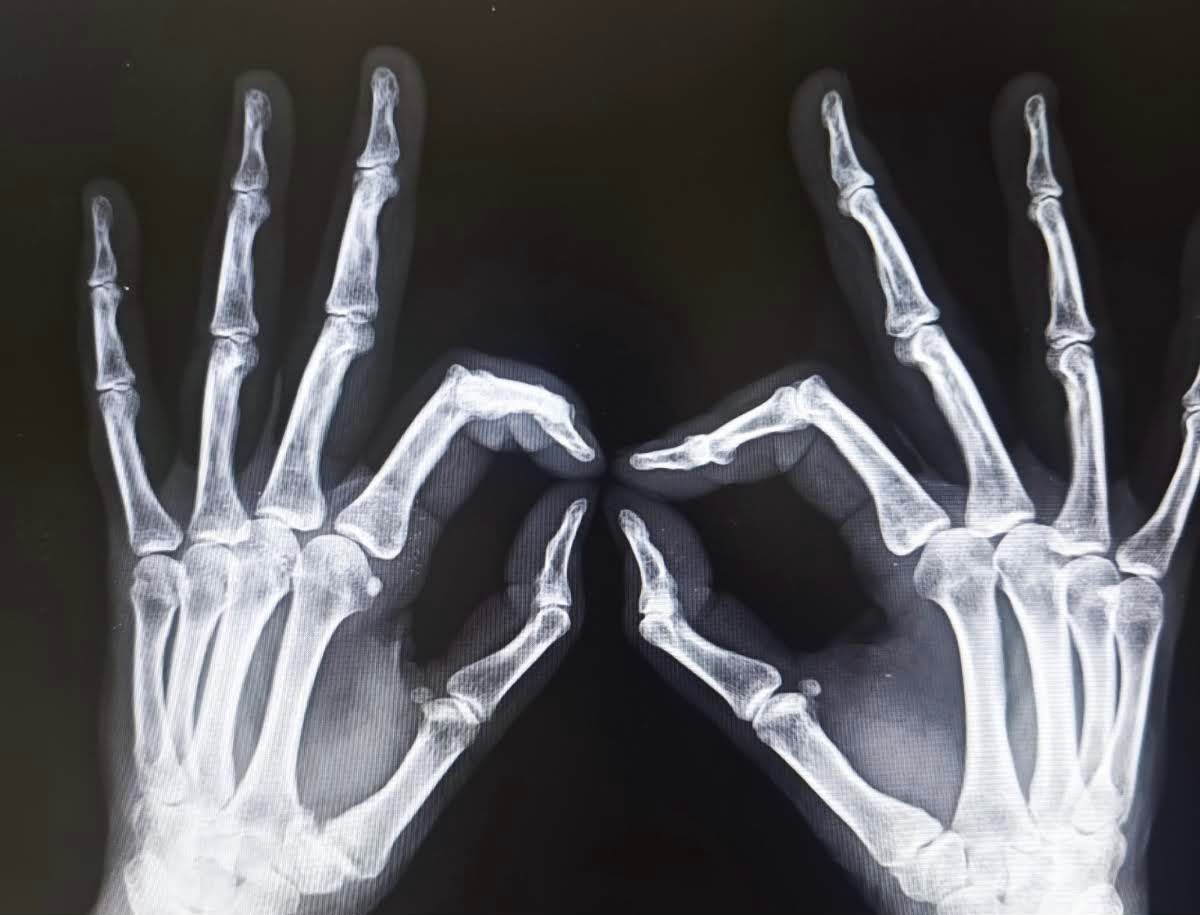

Il Dott. Emanuele Gerace si è laureato in Medicina e Chirurgia presso l'Universita di Roma "La Sapienza" con voto di 110/110 e lode, poi si è specializzato con lode in "Ortopedia e Traumatologia" presso l'Università di Ferrara. Ha completato il suo percorso formativo in Francia presso l'Institut de la Main di Nantes, il Kaplan Hand Institut di Barcellona in Spagna ed in Italia nel centro di chirurgia della mano dell'Hesperia Hospital di Modena e nel centro di chirurgia artroscopica e mini invasiva del ginocchio e della spalla. Nel 2022 ha conseguito il Diploma avanzato di Microchirurgia presso la Società Italiana di Microchirurgia. Si è formato in Artroscopia di polso presso l'IRCAD di Strasburgo, Francia. Ha lavorato per 5 anni come Dirigente Medico presso l'Ospedale Maggiore di Cremona. L'ambito di interesse primario è la chirurgia della mano e del polso. Attualmente svolge la propria attività clinica e chirurgica presso la Fondazione Policlinico Gemelli IRCCS.

Esperto in Chirurgia della Mano.

• Frattura

Mi ha operato di frattura scomposta di polso il mese scorso e ora ho ricominciato a fare tutto senza dolore e senza problemi.

Mi ero rotto il polso e mi ha operato il dott. Gerace con un ottimo risultato. Preciso nelle spiegazioni.